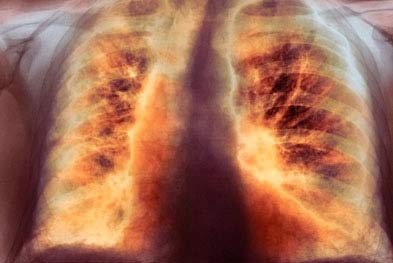

Легкие

Примерно семьдесят процентов пациентов с диагнозом системная склеродермия сталкиваются с поражением легких, что может проявляться в виде интерстициального фиброза (разрастания интерстициальной ткани, являющейся одной из форм соединительной ткани) или легочной гипертензии.

Фиброз легочной ткани вызывает симптомы дыхательной недостаточности, такие как усиливающаяся одышка и сухой кашель без выделения мокроты. Подобные проявления также характерны для легочной гипертензии у этих пациентов.